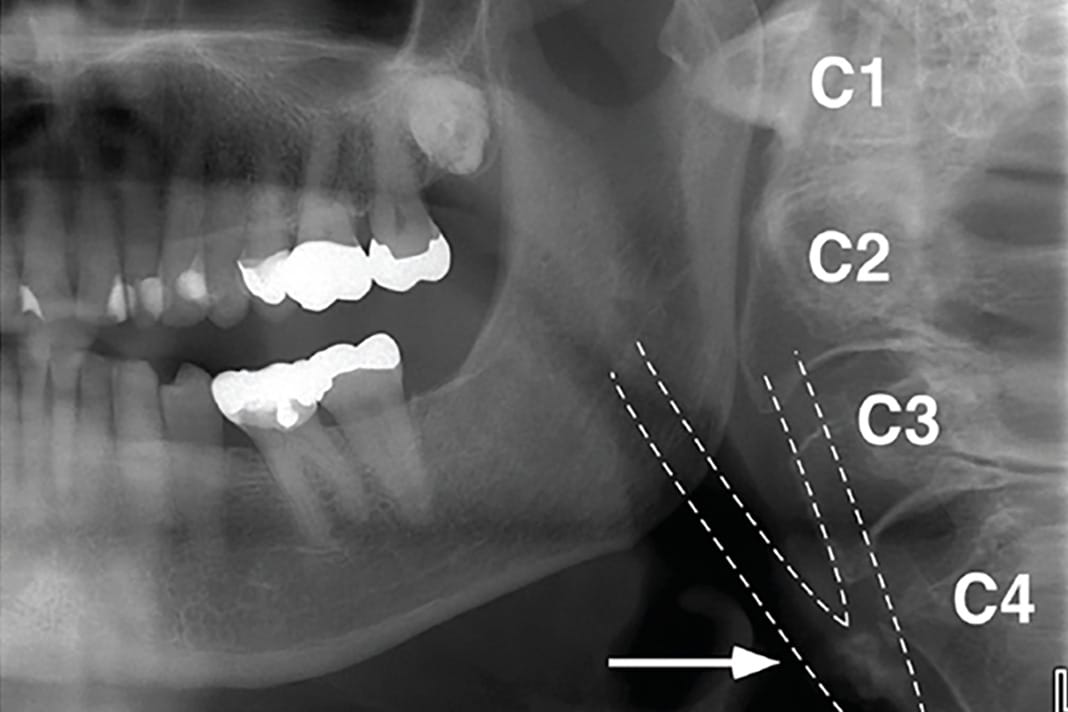

On a PAN, carotid artery calcification (CAC) can appear as a radiopaque lesion that is either rounded or nodular in shape (see Images 1 and 2).9,10 CACs most often present themselves between the C3 and C4 vertebrae. They can be localized to one side or appear bilaterally.10 Moshfeghi et al. stated, “Panoramic radiographs may help us to detect CACs in patients with or without other associated risk factors.”10 This means dental hygienists may be the first ones to discover these in their patients.

area of the carotid bifurcation in a 78-year-old female patient. Image courtesy and used with permission from Kalid Aziz, DDS, MS, and Lucinda J. Lyon, RDH, DDS, EdD.9